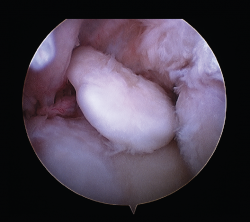

Las patologías más habituales tratadas por medio de una artrolisis artroscópica incluyen: la sinovectomía parcial, el desbridamiento intraarticular de adherencias o lesiones condrales y la liberación capsular y/o capsulotomía anterior y posterior. Los cuerpos libres se pueden extraer y también resecar los osteofitos, frecuentemente situados en coronoides, olécranon o en la foseta olecraneana humeral (Figura 4).

Los principales beneficios del método artroscópico son la agresión quirúrgica limitada, un inicio más precoz de la rehabilitación y la revisión detallada de la patología intraarticular. Este procedimiento es técnicamente exigente, precisa del uso de al menos 2 portales anterolaterales y mediales para abordar la cara anterior del codo (liberación capsular, limpieza de la fibrosis de la cabeza del radio, exéresis de cuerpos libres) y al menos 2 portales posteriores para trabajar en la foseta olecraneana, la parte posterior de la cabeza del radio y en la inserción del tríceps.